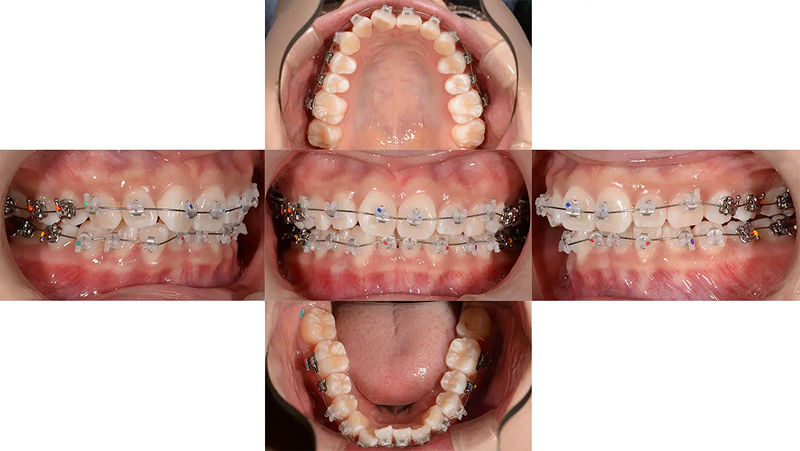

Case03左下の奥歯がとてもしみるを改善した症例

左下第1大臼歯の歯髄炎を主訴に来院されました。第2大臼歯が倒れこんでいるため、治療はできるが、歯質を多量に削合する必要があり、また、今後もむし歯リスクが高い状態が継続します。この環境から脱出するために歯列矯正を提案しました。倒れこんでいた下顎第2大臼歯は左右ともに整直し、過蓋咬合も改善しました。

初診 2017.8.1

矯正開始 2017.10.18

ファイナル 2019.8.12

| 主訴 | 左下の奥歯がとてもしみる |

|---|---|

| 診断 | 両側アングル1級の叢生を伴う過蓋咬合 |

| 矯正方法 | 矯正用アンカーを用いたマルチブラケット |

| 矯正期間 | 24か月・26回 |

| 費用 | 730,000円(税別) |

| 調整料 | 月1回 5,000円(税別) |